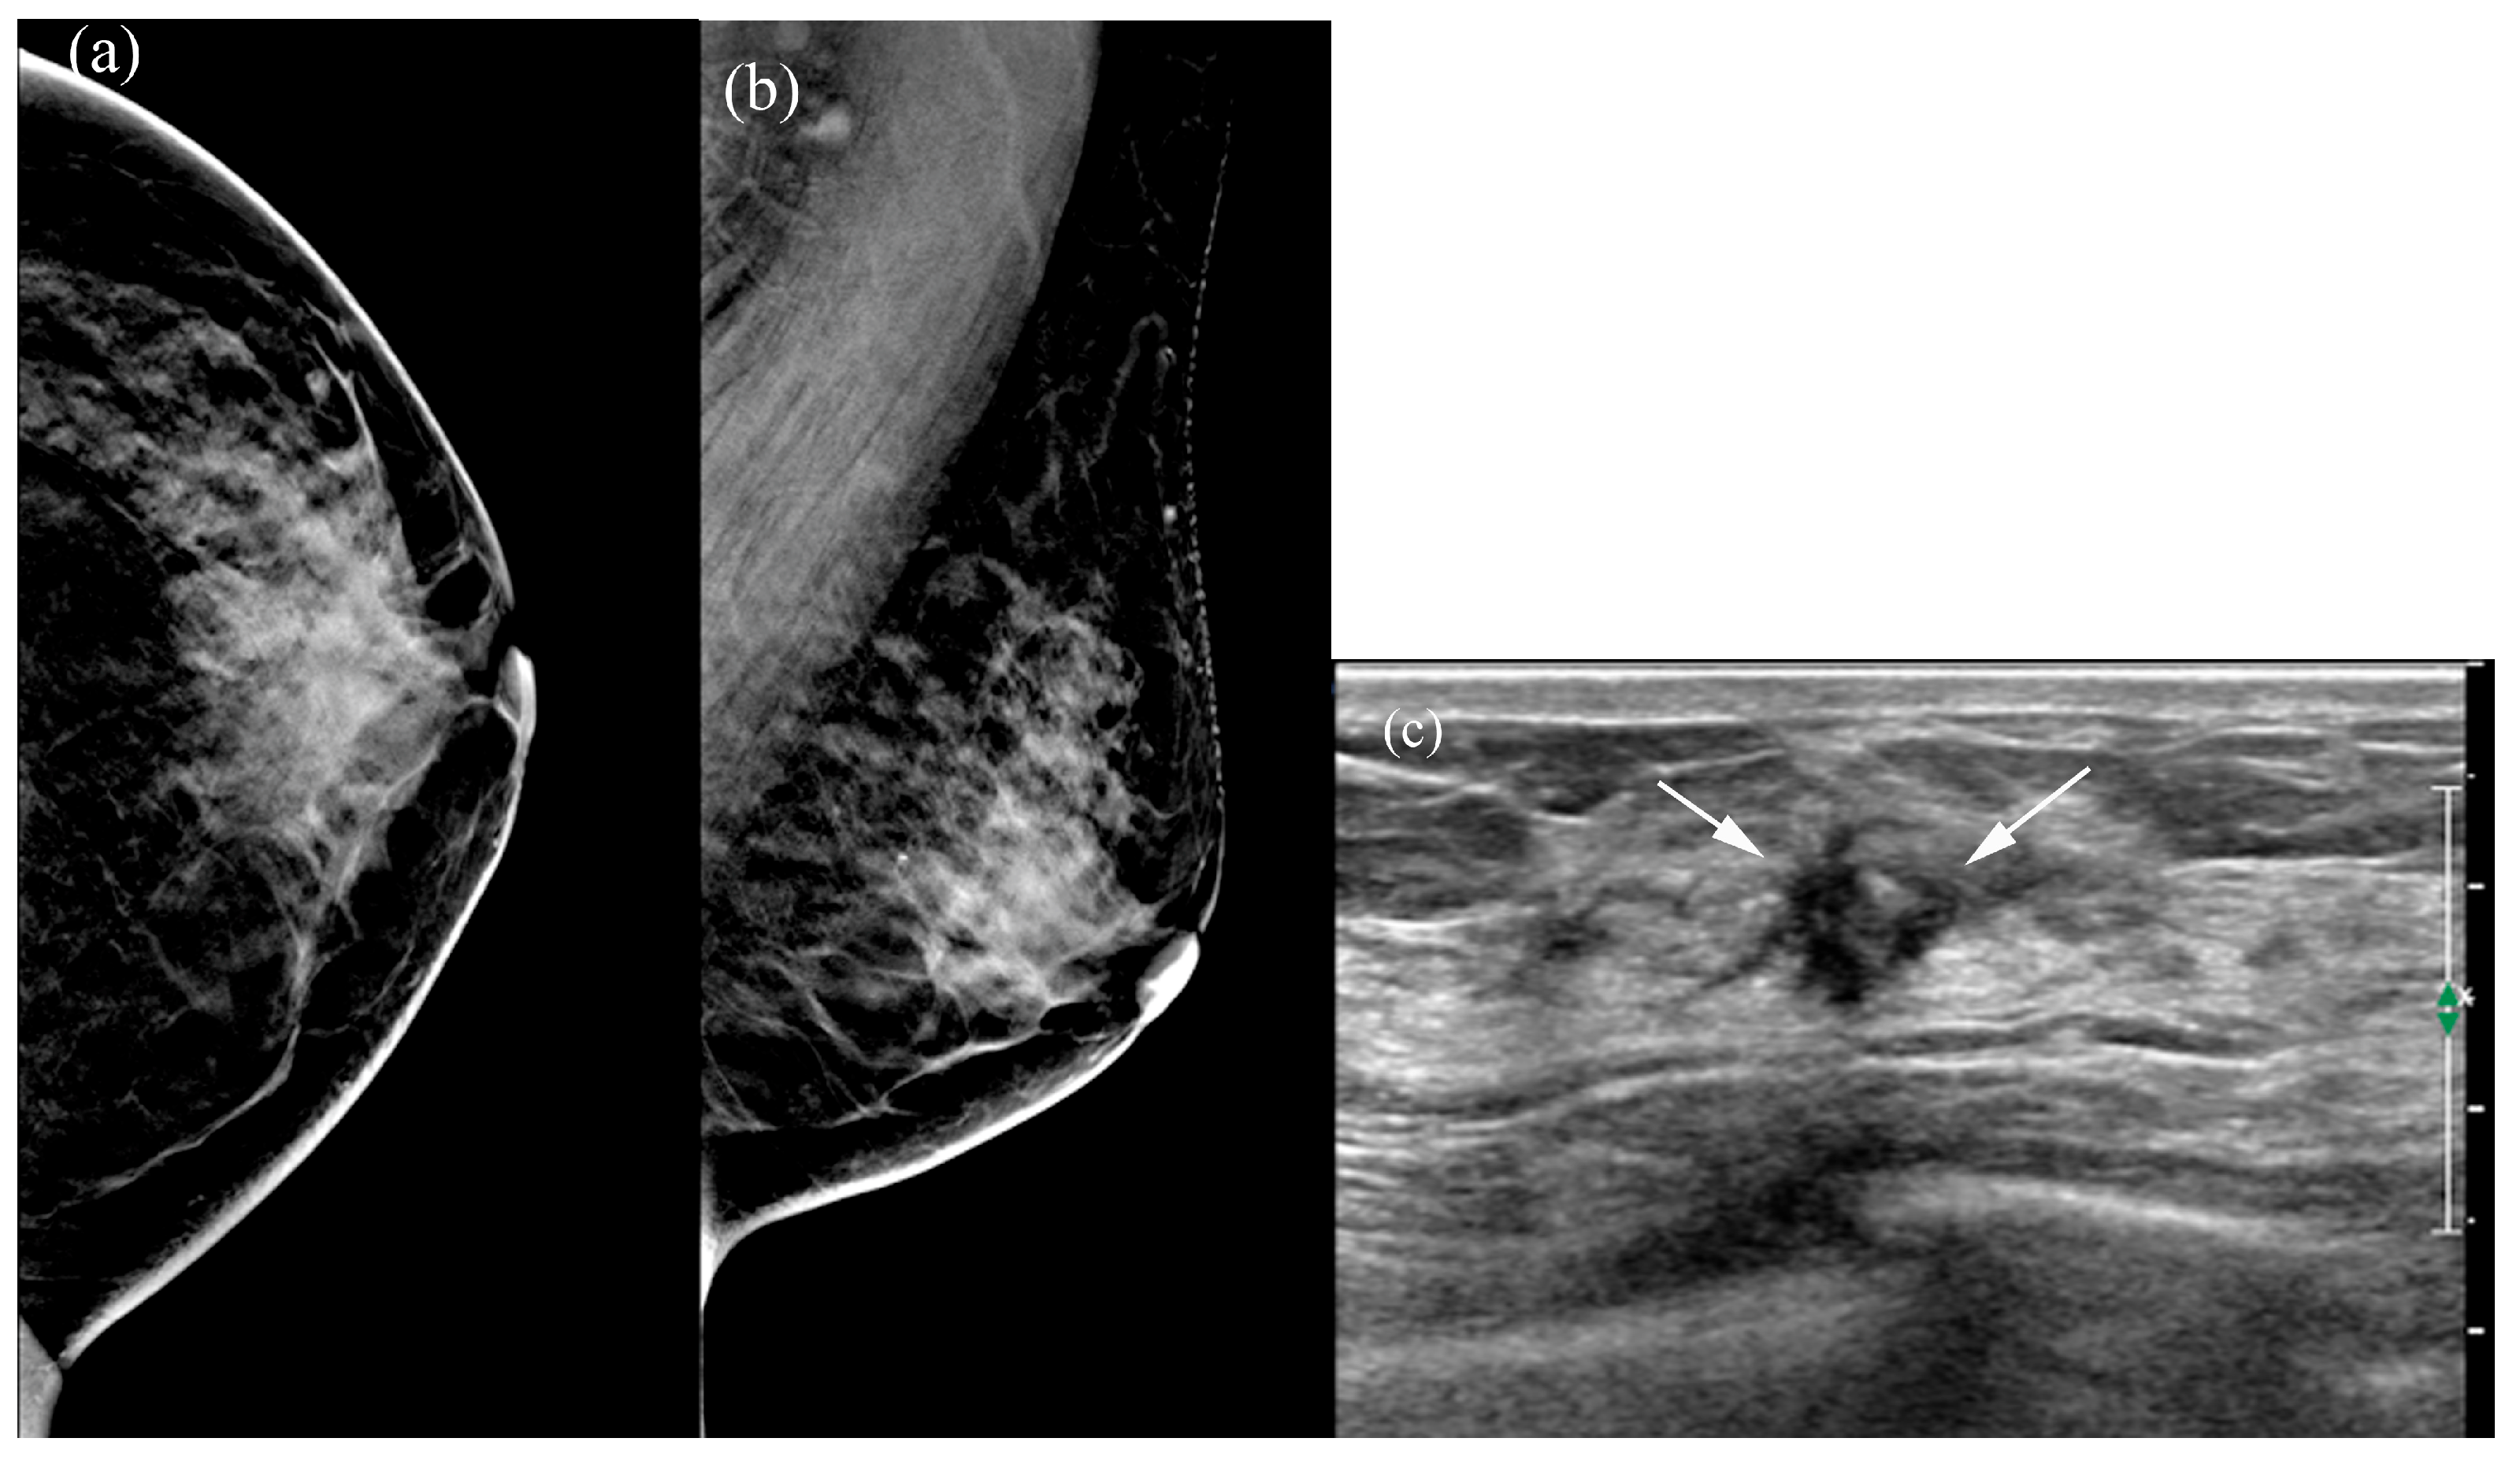

Table 5 summarizes the factors influencing lesion visibility on DBT and MammouS-N images. Lesions that were better visualized on MammouS-N included masses obscured on DBT and non-calcified lesions (p ≤ 0.005) (Figure 4 and Figure 5). Reviewer 2’s assessment showed that larger lesions tended to be better visualized using DBT. No significant associations were observed between lesion visibility and factors such as patient age, mammographic density, lesion size on MammouS-N, echotexture, or lesion type (Figure 6).

Figure 5. A 50-year-old female patient with left-sided bloody nipple discharge: (a,b) The malignancy is not visualized on digital breast tomosynthesis (DBT). (c) Hand-held ultrasound reveals an indistinct, oval hypoechoic mass (arrows) in the left 3 o’clock area. (d) MammouS-N transverse posteroanterior image shows an indistinct, oval hypoechoic mass (arrows) in the left 3 o’clock area (A, anterior; P, posterior; M, medial). Surgical pathology confirmed microinvasive secretory carcinoma.